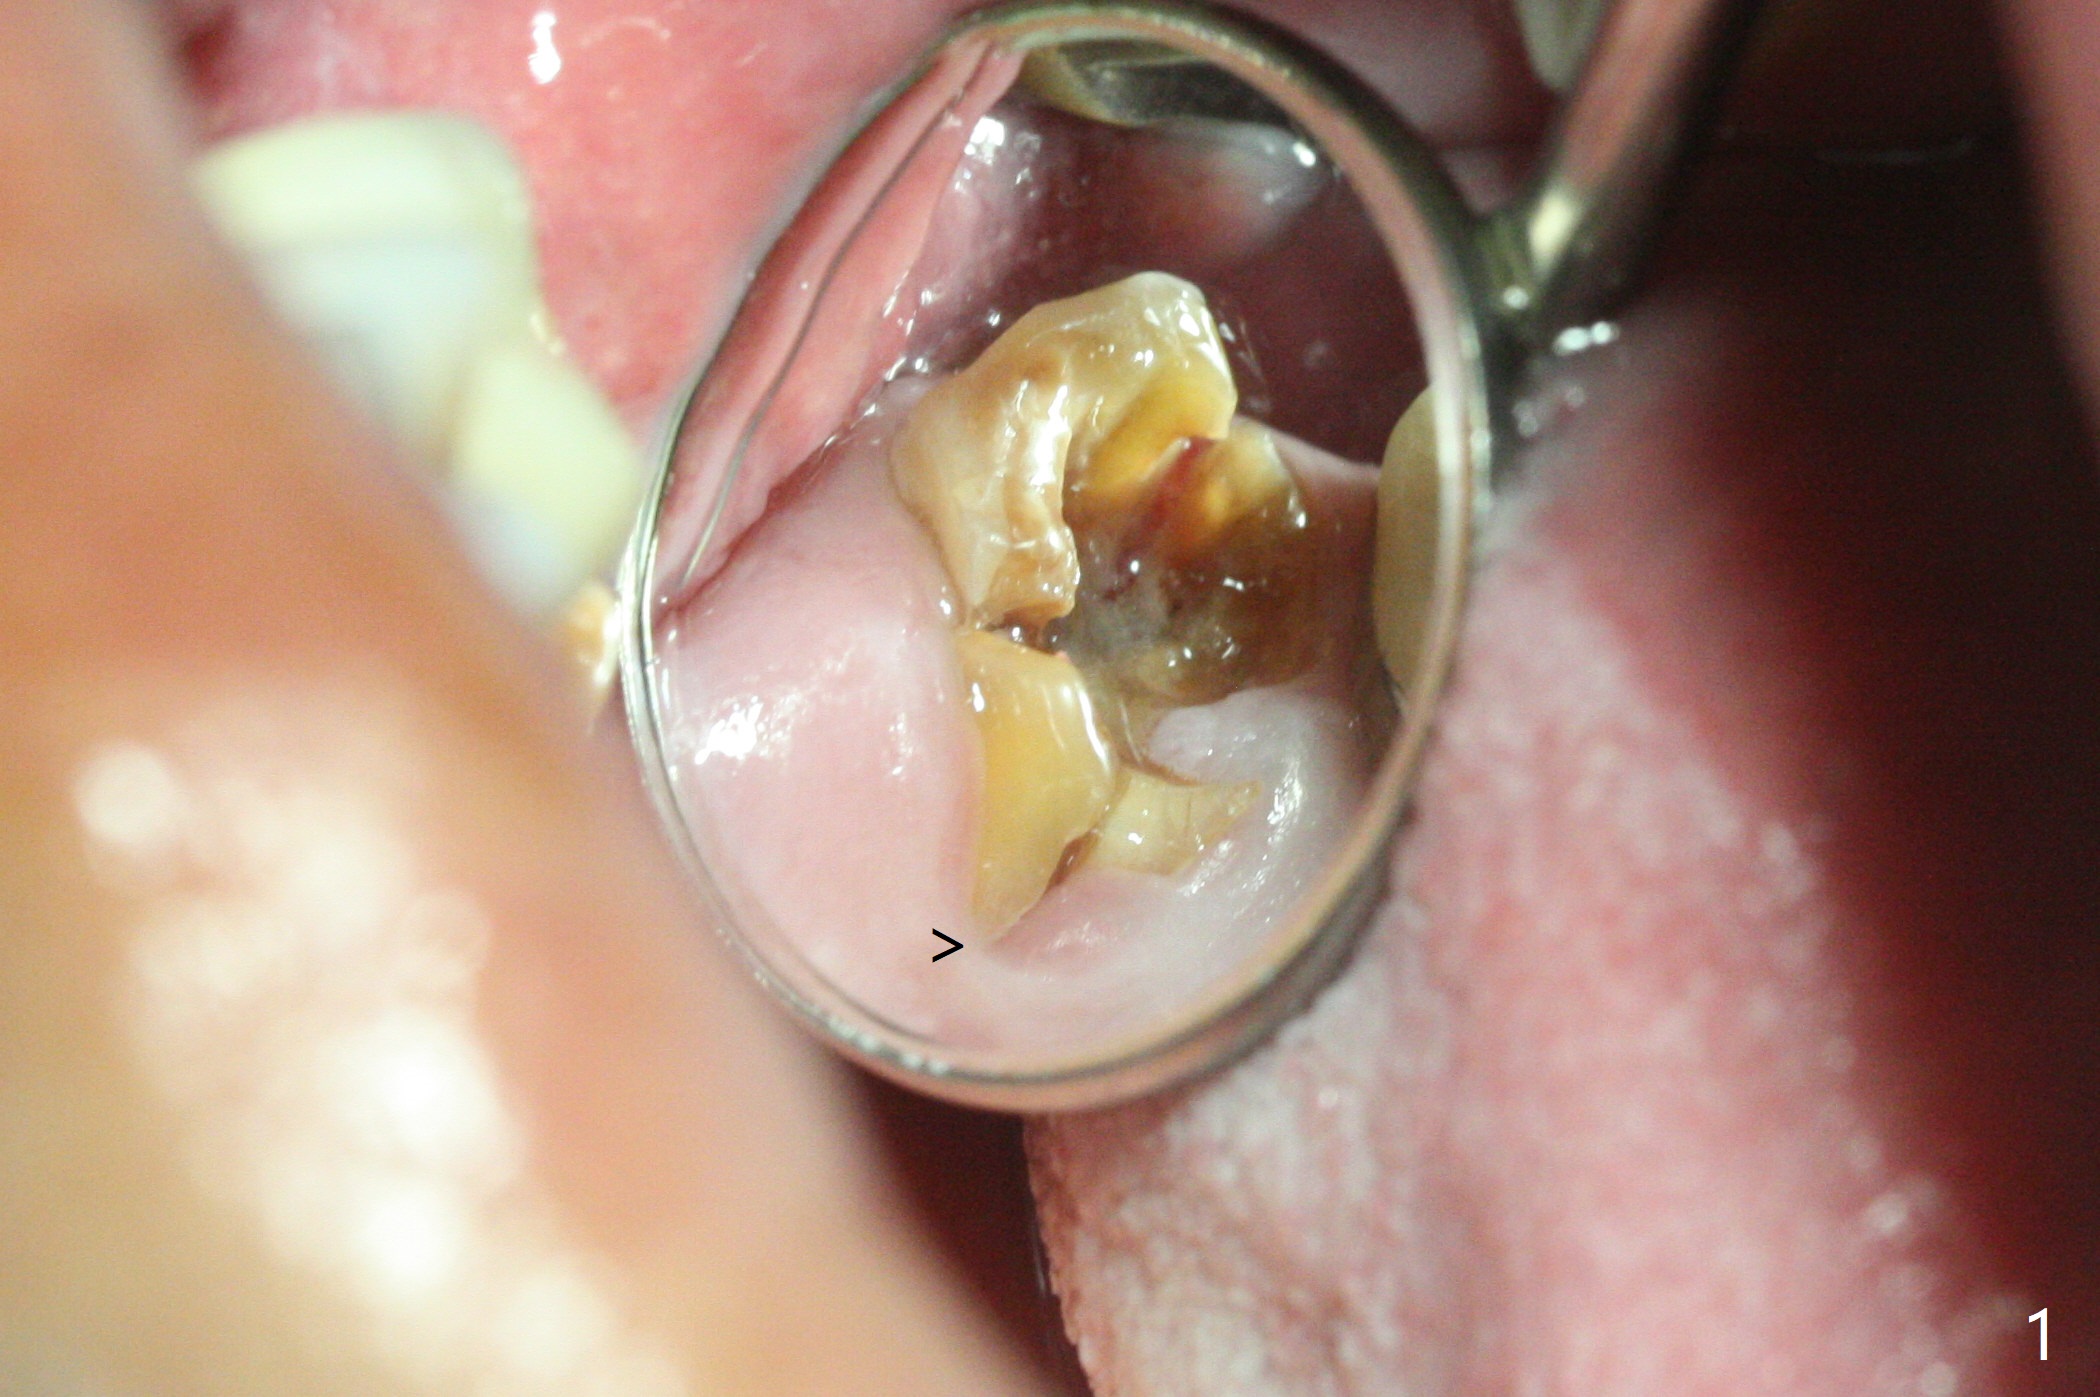

The palatal gingival margin of the tooth #15 with vertical root fracture is low, consistent with the low palatal plate after extraction (Fig.1 >). With IS guide, a 5x11 mm IBS implant is placed in the septum with >5 mm the palatal gap. After underprep in depth, a 3.5x9 mm achieves primary stability (Fig.2,3). The palatal defect is repaired with allograft (*) and 2 pieces of PRF membrane. The palatal soft tissue defect appears to have been repaired 6 months postop (Fig.4,5). When a narrower abutment with longer cuff is placed at #15 (6x4(4) mm in Fig.6, as compared to 6.5x4(3) mm one in Fig.2), there is no gap between the implant and abutment. In contrast there is one at #13 (Fig.6 <) when a 4x4(4) mm abutment is seated following removal of a 4x4 mm healing abutment. After use of a 4.6 mm profile drill, the gap disappears (Fig.7). Impression is taken.